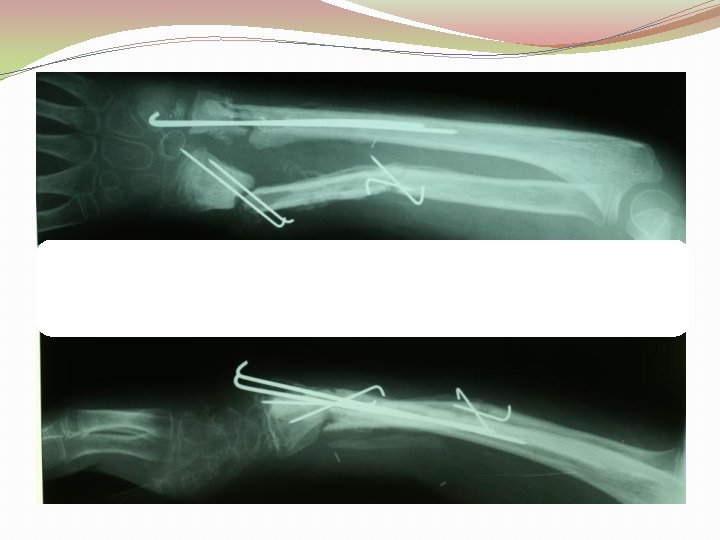

Ķirurģiska ārstēšana Osteomielīta pacientiem jāveic radikāls debridement ķirurģiski, kas ietver visu procesā iesaistīto audu rezekciju: �Mīksto audu rētas rezekcija �Cīpslu kalcinātu rezekcija �Distantu sekvestru rezekcija �Kaula rezekcija līdz vizuāli veseliem audiem – readzama punktveida asiņošana ´Paprika sign’. Bogdan Maciuceanu, Lucian Jiga, Alexandru Nistor, Jenel Marian Pastrascu, Mihail Ionac Chronic Osteomyelitis of Long Bones Timisoaral Medical Jornal, 2005